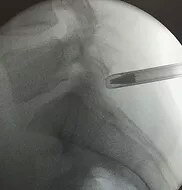

Рабочая канюля (порт) в область расположения грыжи позвоночника устанавливается под контролем рентгеноскопии в двух проекциях, что обеспечивает полную безопасность доступа к позвоночной грыже. Непосредственно во время операции удаления позвоночной грыжи, при необходимости, осуществляется дополнительный контроль положения инструмента.

На первых двух рентген-изображениях ниже показан трансфораминальный доступ, на последнем изображении с краю показан интерламинарный доступ.